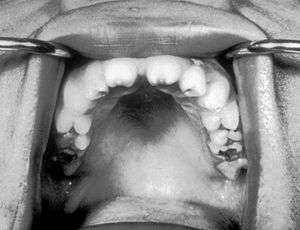

| Notched incisors known as Hutchinson's teeth which are characteristic of congenital syphilis | |

- blunted upper incisor teeth known as Hutchinson's teeth

A frequently-found group of symptoms is Hutchinson's triad, which consists of Hutchinson's teeth (notched incisors), keratitis and deafness and occurs in 63% of cases.[4]

- Hutchinson's triad, a set of symptoms consisting of deafness, Hutchinson's teeth (centrally notched, widely spaced peg-shaped upper central incisors), and interstitial keratitis (IK), an inflammation of the cornea which can lead to corneal scarring and potentially blindness.